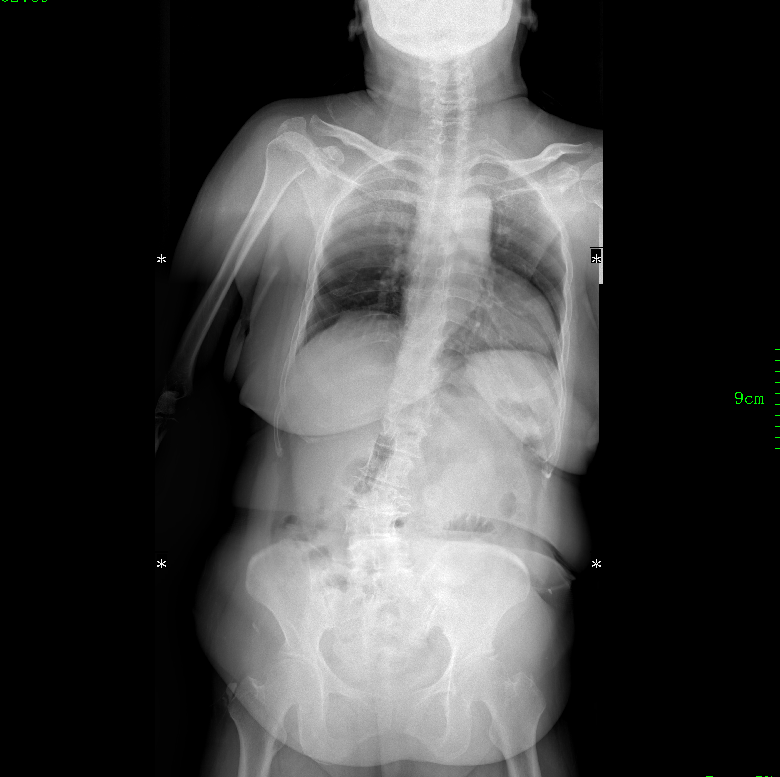

經(jīng)過詳細(xì)的影像學(xué)檢查,醫(yī)生發(fā)現(xiàn)患者存在腰椎退行性脊柱側(cè)彎,側(cè)彎角度超過30度。